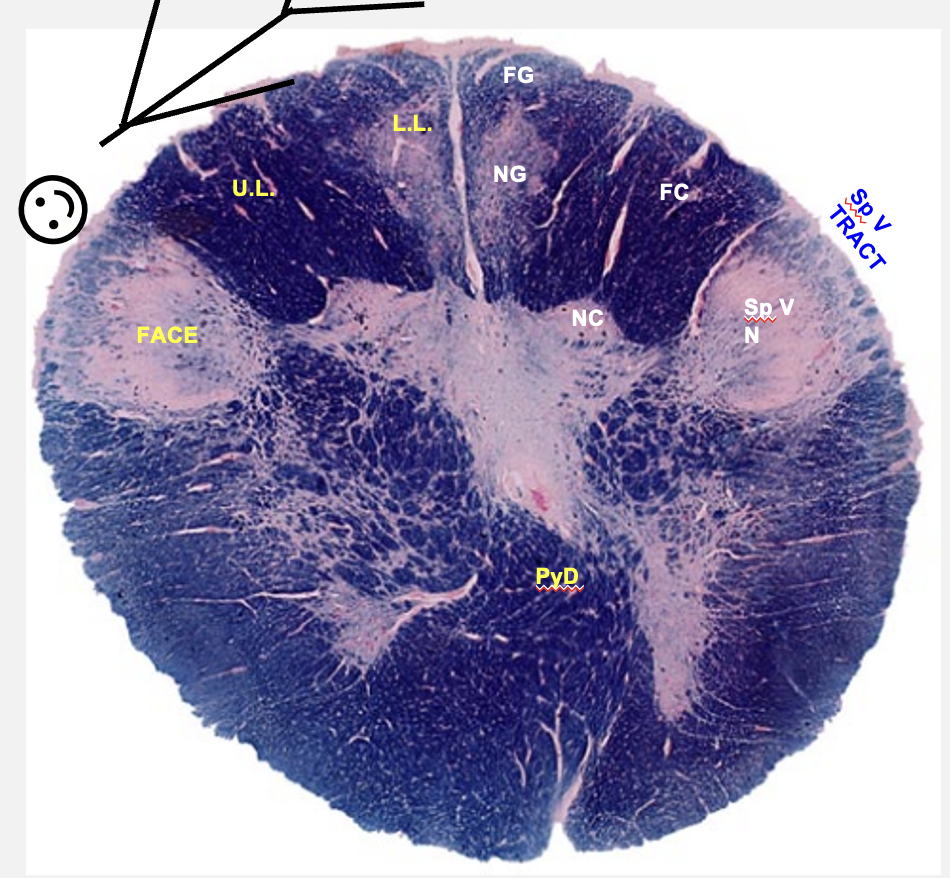

cervical spinal cord cross-section structures

fasiculus gracilus

nucleus gracilus

fasiculus cuneatus

nucleus cuneatus

spinal nucleus of V

spinal tract of V